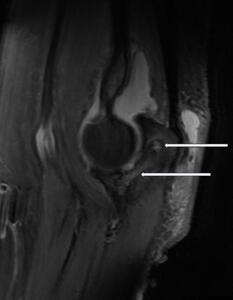

The MRI, performed 5 days later, demonstrated bone marrow high signal, confirming the suspicion of chronic olecranon osteomyelitis, with decompression into the olecranon bursa via a dorsal cloaca (Figure 2). With no evidence of hypointense tumor marrow involvement, bony neoplasm was considered less likely than osteomyelitis following MRI. The MRI also suggested decompression into the joint through the olecranon articular surface, and identified moderate joint effusion and olecranon bursitis with a 0.8 cm ossific body.